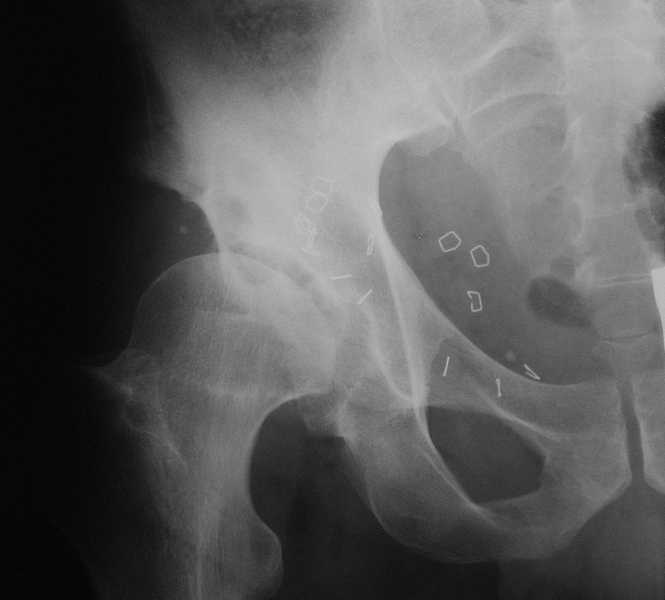

Картина типичной эволюции дисплазии сустава "кистовидная перестройка", на фоне неправильного взаймоотношения сустава "да тут угол Виберга 0 градусов" на вершине наибольшей нагрузки в вертлужной впадине образовался участок разрежения, "киста", в последующем через этот участок образуется перелом - стадия фрагментация дисплазии.

Для установки диагноза достаточно информации, на рентгенограмме передний и задний край ацетабулум образовали перекрест, "цифру восемь", указывающий на небольшую ретроверсию, а суставная щель одинаковой ширины на всем протяжении, что доказывает, что с покрытием хряща проблем нет. Головка бедра покрыта всего наполовину, это явное нарушения взаимоотношений.

Неоднократные обсуждения на форуме "пропущенных переломов" показывает, что короткие урезанные снимки приводят к ошибке, тем более у данного больного для решения тактики лечения необходимо детальное исследование суставов.

А для данного случая, необходим прямой снимок таза с отдельными суставами, также включить боковые снимки сустава, немаловажно знание покрытия головки спереди.